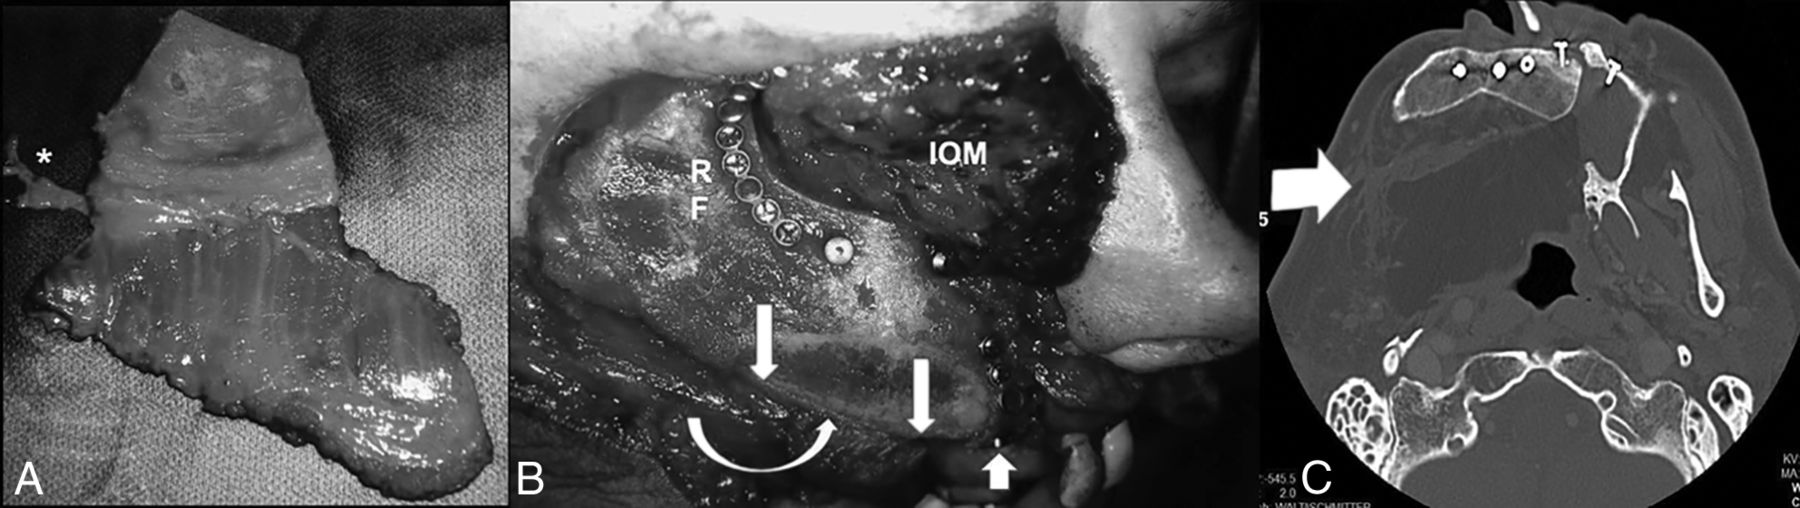

A, An iliac crest–internal oblique flap has been harvested based on the DCIA and DCIV (asterisk). B, The iliac crest is shown inset into a palatomaxillectomy defect with the crest oriented toward the bottom (arrow). The internal oblique muscle based on the ascending branch of the DCIA has been brought through the palatal defect, medial to the iliac bone (curved arrow). This patient underwent an orbital exenteration, and the internal oblique muscle (IOM) is shown filling the orbital defect as well as obliterating the maxillectomy cavity. Rigid fixation (RF) is achieved to the lateral and superior orbital rim. The upgoing arrow shows a dental implant placed into the neoalveolar ridge. C, The internal oblique muscle, which is not optimally visualized on bone window, is used to fill the maxillectomy defect (arrow).

Use of ICFF with internal oblique muscle (A) and orbital floor plate. The iliac bone is used to restore the inferior orbital rim as well as to reconstruct the pyriform aperture. An onlay bone graft is lag screwed into the iliac bone to restore the anterior projection of the midface (B and C). The curvature of the neomaxilla has been created by performing a unicortical osteotomy and filling it with corticocancellous bone followed by a fixation plate to hold it in position. The internal oblique muscle is used to reline the lateral wall of the nose and obliterate the maxillectomy cavity (D and E). The muscle is transposed through the palatal defect to achieve a permanent separation of the mouth from the sinonasal cavity. Illustration by Jill Gregory. Used with permission from ©Mount Sinai Health System.